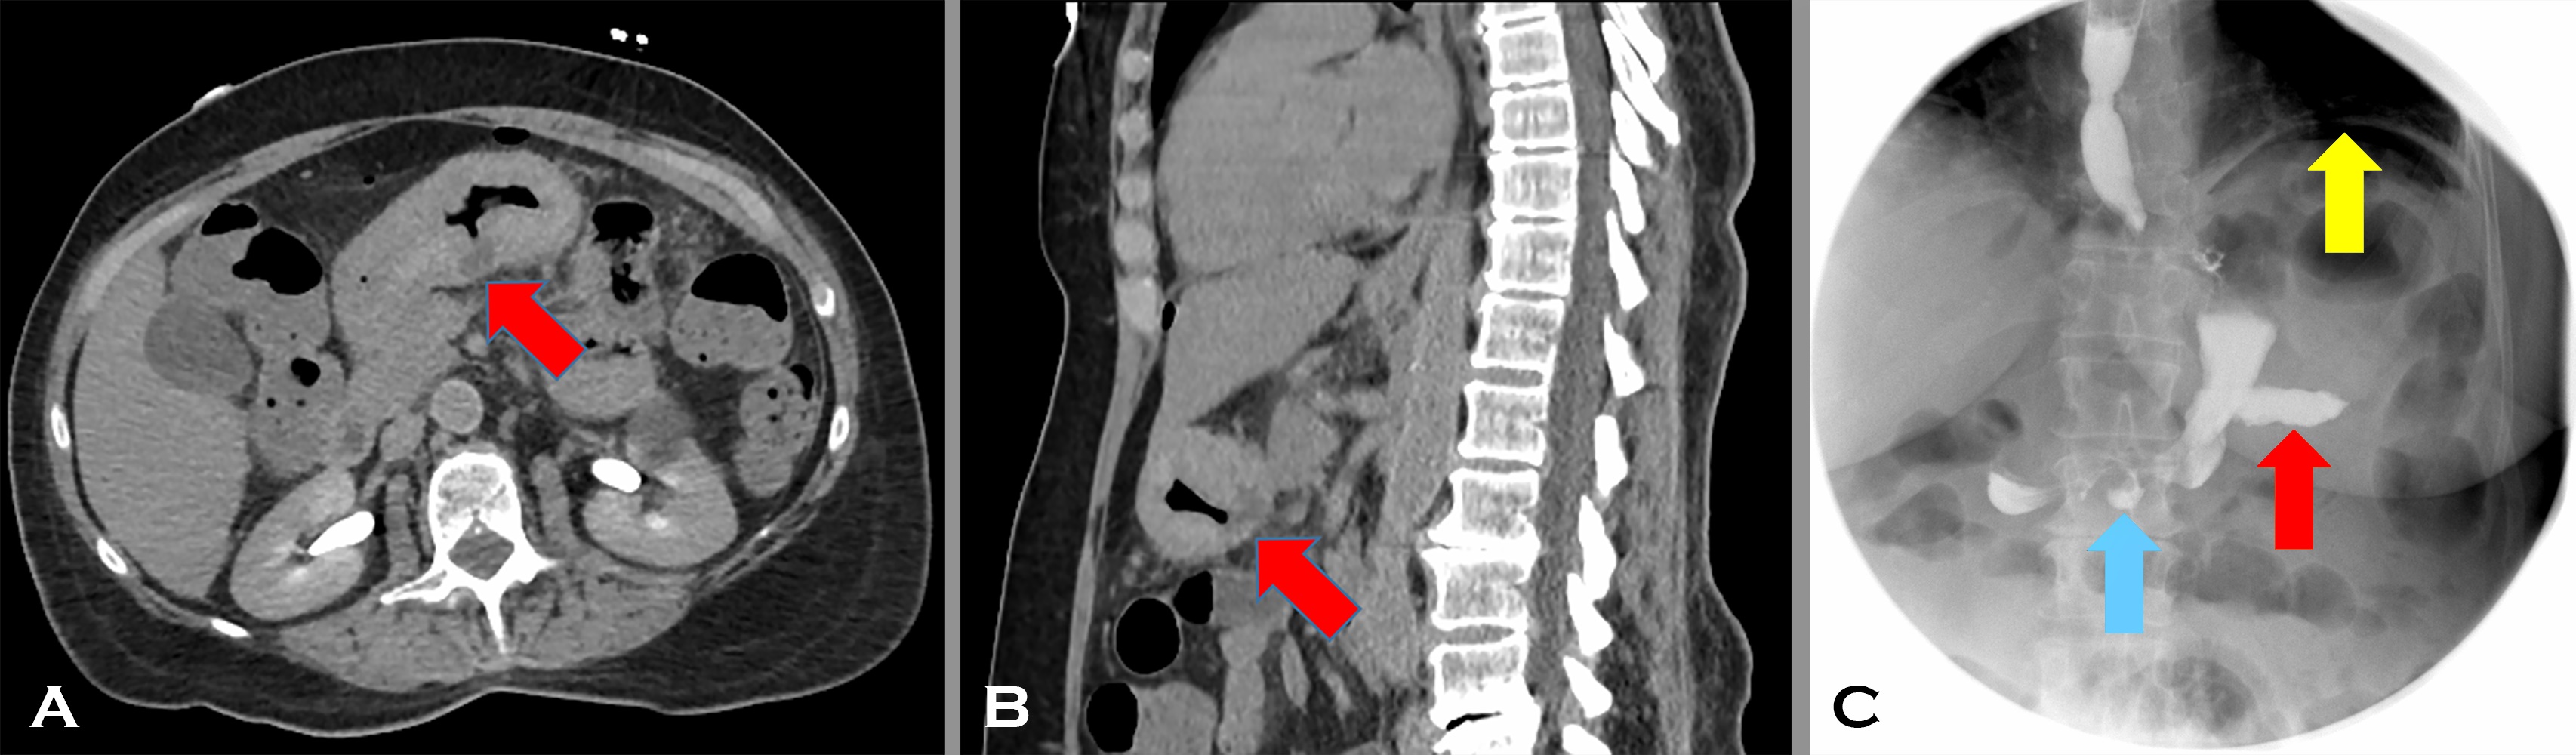

In our case, following diagnosis on the biopsy, perioperative chemotherapy with 3 cycles of 5-flurouracil, leucovorin, oxaliplatin, and docetaxel (FLOT) was planned. However, after just one cycle, the patient’s clinical course became complicated with severe abdominal pain. A CT scan of the abdomen/pelvis with no intravenous or oral contrast showed a perforated antral ulcer (Image 4 A axial and B sagittal reconstructions, with Red arrows indicating the full thickness gastric wall defect). Findings were confirmed on a water-soluble contrast swallow test (Image 4 C: Blue arrow indicating the ulcer and Red arrow indicating extraluminal contrast layering in the peritoneal cavity). Free intraperitoneal air due to perforation was also evident (Image 4 C: Yellow arrow). Image 4, composite radiographs A-C.